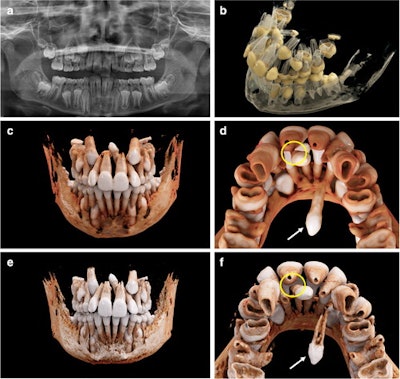

An 11-year-old boy with a mesiodens and a supplementary tooth (white arrows) within the hard palate. (a) An x-ray of the boy’s mouth. (b) A display of the semitransparent reconstruction parameters. (c and d) The bone reconstruction parameters with a soft kernel can lead to artifacts in regions with teeth near each other (yellow circle in d, e, and f.) The same situation is shown with a hard kernel, allowing better differentiation between the roots of the mesiodens and of tooth #21 (yellow circle in f).